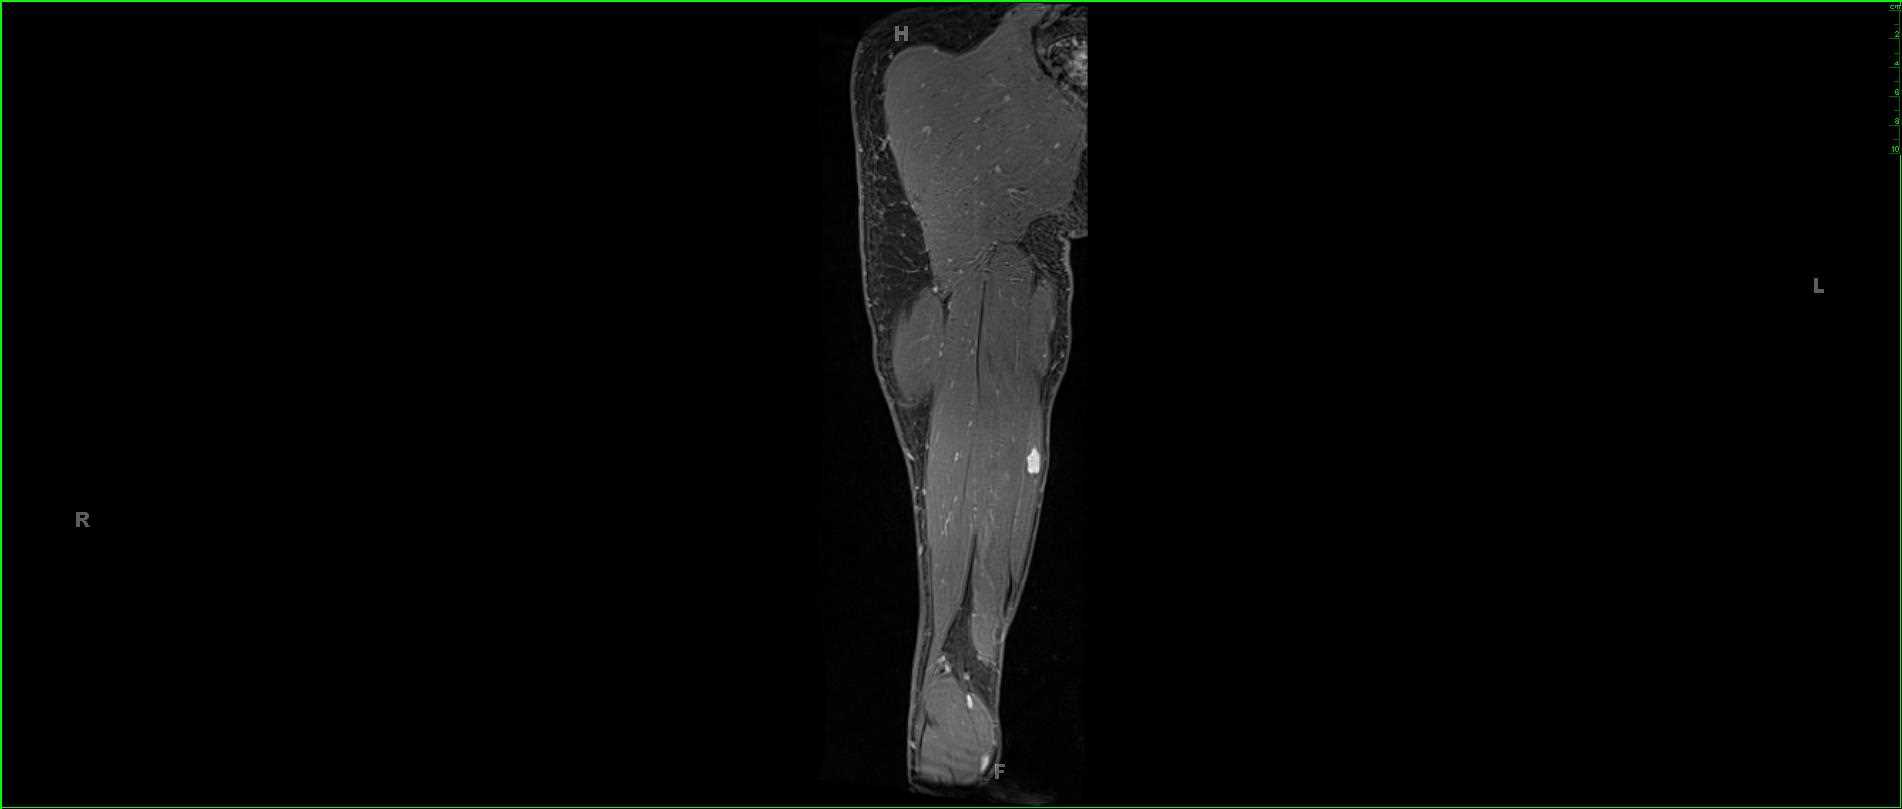

Giant Cell Tumor, Humerus

53-year-old female who presents for chronic left shoulder pain. There is an infiltrative proton density isointense, STIR hyperintense, diffusion restricting and heterogeneously enhancing mass involving the proximal left humerus. There is a complex left shoulder effusion with heterogeneous enhancement. The tumor extends to the proximal left humeral epiphysis. Differential diagnosis includes giant cell tumor, chondroblastoma, chondromyxoid fibroma, metastatic disease and plasmacytoma. On biopsy, this was found to be a giant cell tumor. Giant cell tumors are relatively common benign tumors which are found arising from the metaphyseal regions with extension to the physis of long bones. The peak between 20-30 years of age with a slight female predilection. Presentation is usually insidious and related bone pain, soft tissue mass, compression of surrounding structures and possibly pathologic fracture. Lesions more commonly occur in the distal femur, proximal tibia, distal radius, sacrum and vertebral bodies. Treatment is with curettage and packing.